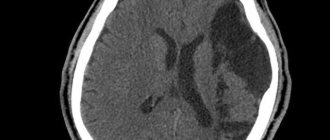

Рис3. Общий вид опухоли мозга в лобной доле на КТ

2. Опухоли мозга обладают эффектом массы, благодаря объёмному воздействий собственной стромы, смещая и раздвигая нормальные анатомические структуры мозга.